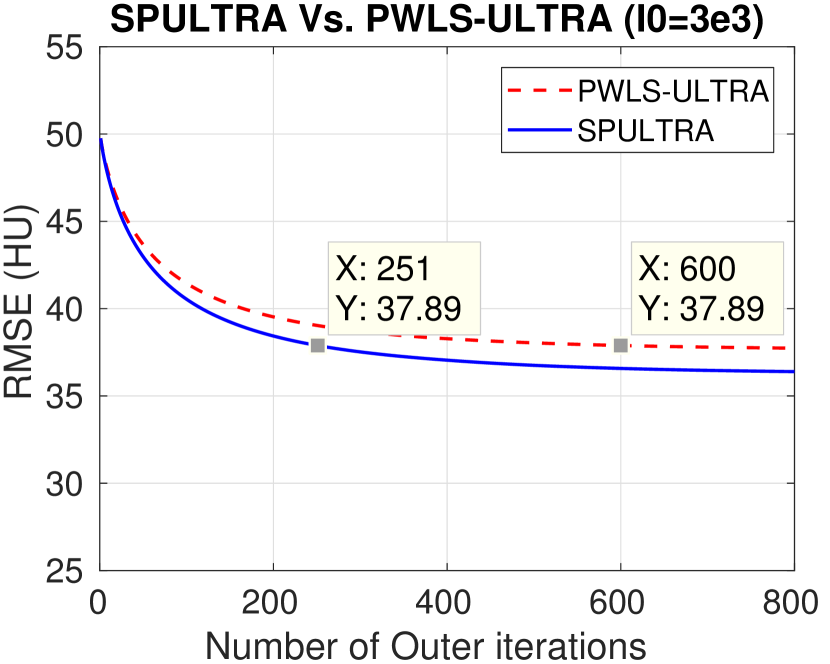

The RMSE improvement of SPULTRA over PWLS-ULTRA can be more clearly observed from Fig. 3 that shows the RMSE evolution with the number of outer iterations under different dose levels. At low-doses, SPULTRA decreases the RMSE more quickly (from the same initial value) and to much lower levels than PWLS-ULTRA. Fig. 3 shows that to achieve the same RMSE as PWLS-ULTRA at 600 outer iterations, SPULTRA takes 487, 365, 251 and 133 outer iterations under , respectively.

V-A4 Computational Costs

As discussed in Sec. III-D, SPULTRA has a similar computational cost per iteration as PWLS-ULTRA, except for computing some initializations for image update. Fig. 3 shows that the SPULTRA method requires much fewer number of outer iterations than PWLS-ULTRA to achieve the same RMSE for the reconstruction, especially at low doses.

When the dose is very low, e.g., when , SPULTRA takes only a quarter the number of outer iterations as PWLS-ULTRA to achieve the same RMSE. Thus, the total runtime to achieve a specific reconstruction quality at low doses is typically much lower for SPULTRA than for PWLS-ULTRA. When the dose is not very low, for example when , the SPULTRA and the PWLS-ULTRA methods have similar computational costs and runtimes. To achieve RMSE of 29.26 HU (see Fig. 3(a)), PWLS-ULTRA requires 600 outer iterations, while SPULTRA requires 487 584 effective outer iterations where the additional runtime is associated with initializations in each SPULTRA outer iteration.